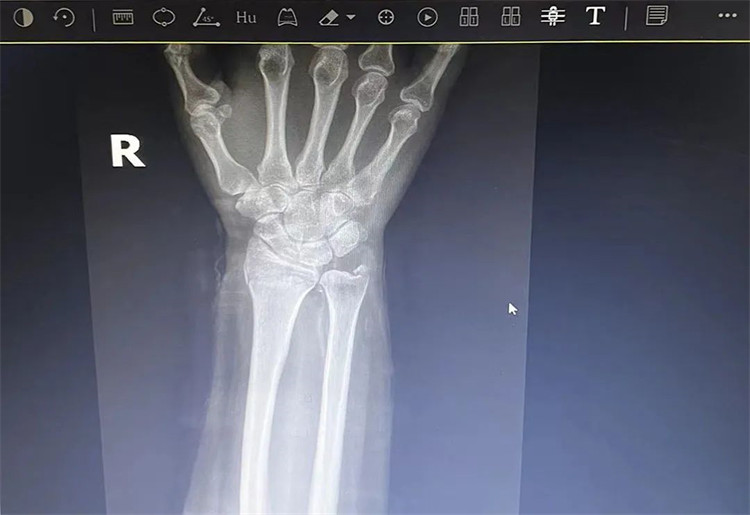

患者老年女性,50多歲,在騎電動車停下時因電動車倒下,右手著地,當(dāng)即感覺,右腕及骶尾部腫痛伴右關(guān)節(jié)畸形、活動受限,急來我院就診。門診醫(yī)師結(jié)合病史、查體及輔助檢查后,診斷為:右橈尺骨遠(yuǎn)端骨折、骶尾部挫傷并收入住院部。

患者入院后,中醫(yī)正骨科副主任鄭斌斌,認(rèn)真查體及分析檢查結(jié)果后,考慮患者老年女性,建議患者采用拔伸牽引、端提、捺正等閉合手法復(fù)位后,行夾板固定,多能獲得較好療效?;颊邚?fù)位固定后,疼痛明顯減輕。避免了手術(shù)帶來的痛苦及手術(shù)開刀所需費(fèi)用。